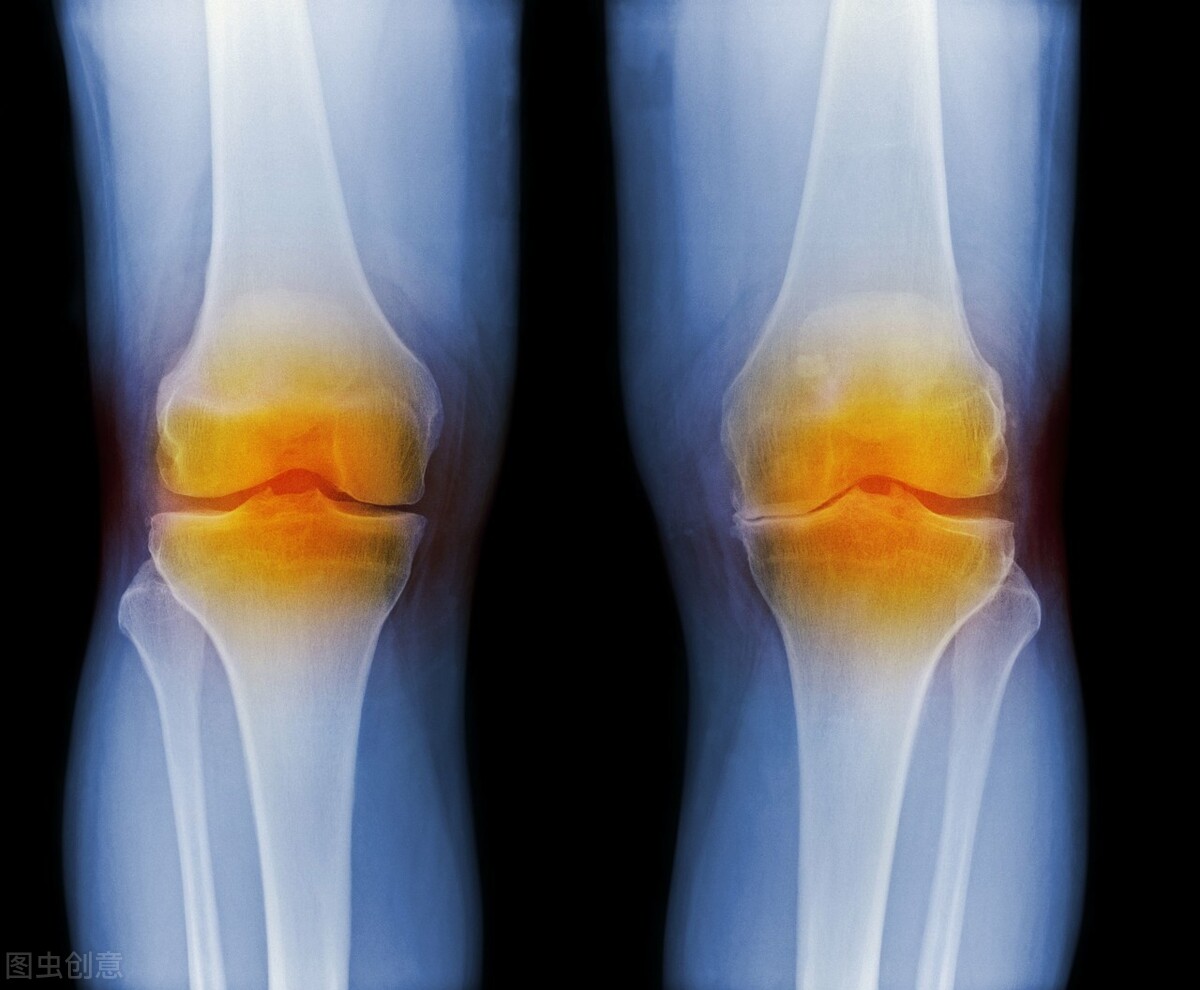

关节退行性病变是骨质增生、骨关节炎的统称,属于关节炎的一种。主要的发病因素是关节因为机械应力分布失衡,负载过度而引起的软骨磨损。多发于老年人。

关节退行性变主要累及负重关节,比如膝关节、髋关节、肩关节以及腰椎、颈椎关节等,引起相应部位的症状和体征。

比如膝关节退化病,可以表现为患者上下楼梯困难,下蹲、起立困难,关节活动的时候有弹响声和骨擦感,严重者局部有明显的肿胀、压痛、活动受限。